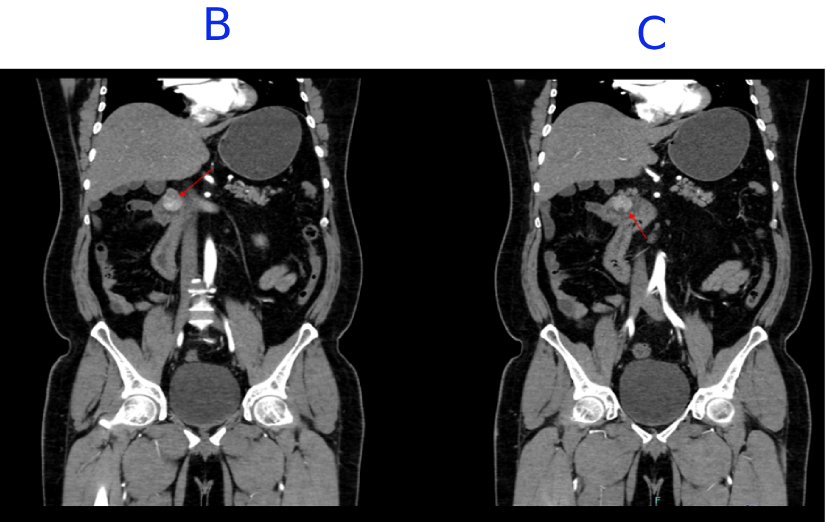

B. Few internal non-enhancing areas are seen in the superior aspect of the lesion.

C. A focal defect seen in the inferior aspect of the lesion, suggestive of ulceration.

D. Incidental note of malrotation with the duodenojejunal junction lying to the right of the midline and altered SMA-SMV relationship.